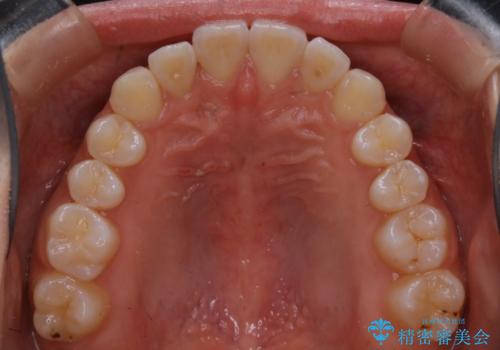

こちらの患者様の場合、上の前歯のガタつきが原因で口を閉じる際に上下の前歯の先端同士が先に当たってしまい、そこからさらに深く噛み込もうとすると下顎が前にずれていってしまうという、機能性の反対咬合であることが検査の結果わかりました。

そのため、まずは上顎の前歯のガタつきを改善していき、前歯が先に当たってしまうという症状を改善し噛み込む位置を後方の本来の位置に誘導する方法をとりました。